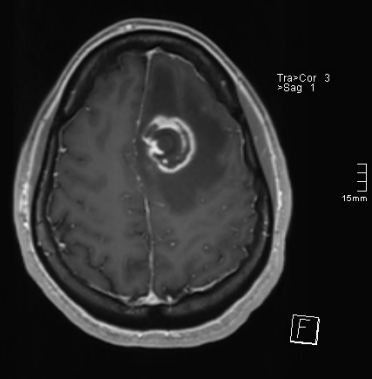

Helena, mulher cis, 56 anos, é levada ao pronto atendimento devido a episódio de fraqueza súbita em membro inferior direito, que dificultou a marcha, há cerca de 6 horas, evoluindo com crises convulsivas. O acompanhante informa que a paciente é acompanhada em UBS por hipertensão arterial, dislipidemia e diabetes mellitus, com antecedente de AVE isquêmico há 8 anos, do qual se recuperou sem déficits. Ao exame neurológico, apresenta Glasgow 14, déficit neurológico focal restrito a membro inferior direito, preservando força nos demais membros, sem alteração de fala, com reflexos pupilares normais, sem desvio de rima labial e ausência de sinais de irritação meníngea. Sinais vitais estáveis, exceto temperatura axilar de 37,7°C. Teste rápido para HIV na admissão foi reagente. Realizada RM de crânio abaixo.

Enunciado 4938421-1

O diagnóstico mais provável para este caso é